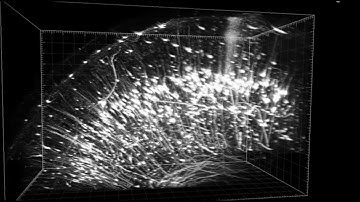

OpenLiver HepaRG NP 3D: MDR1 Labeling and Tissue Clearing